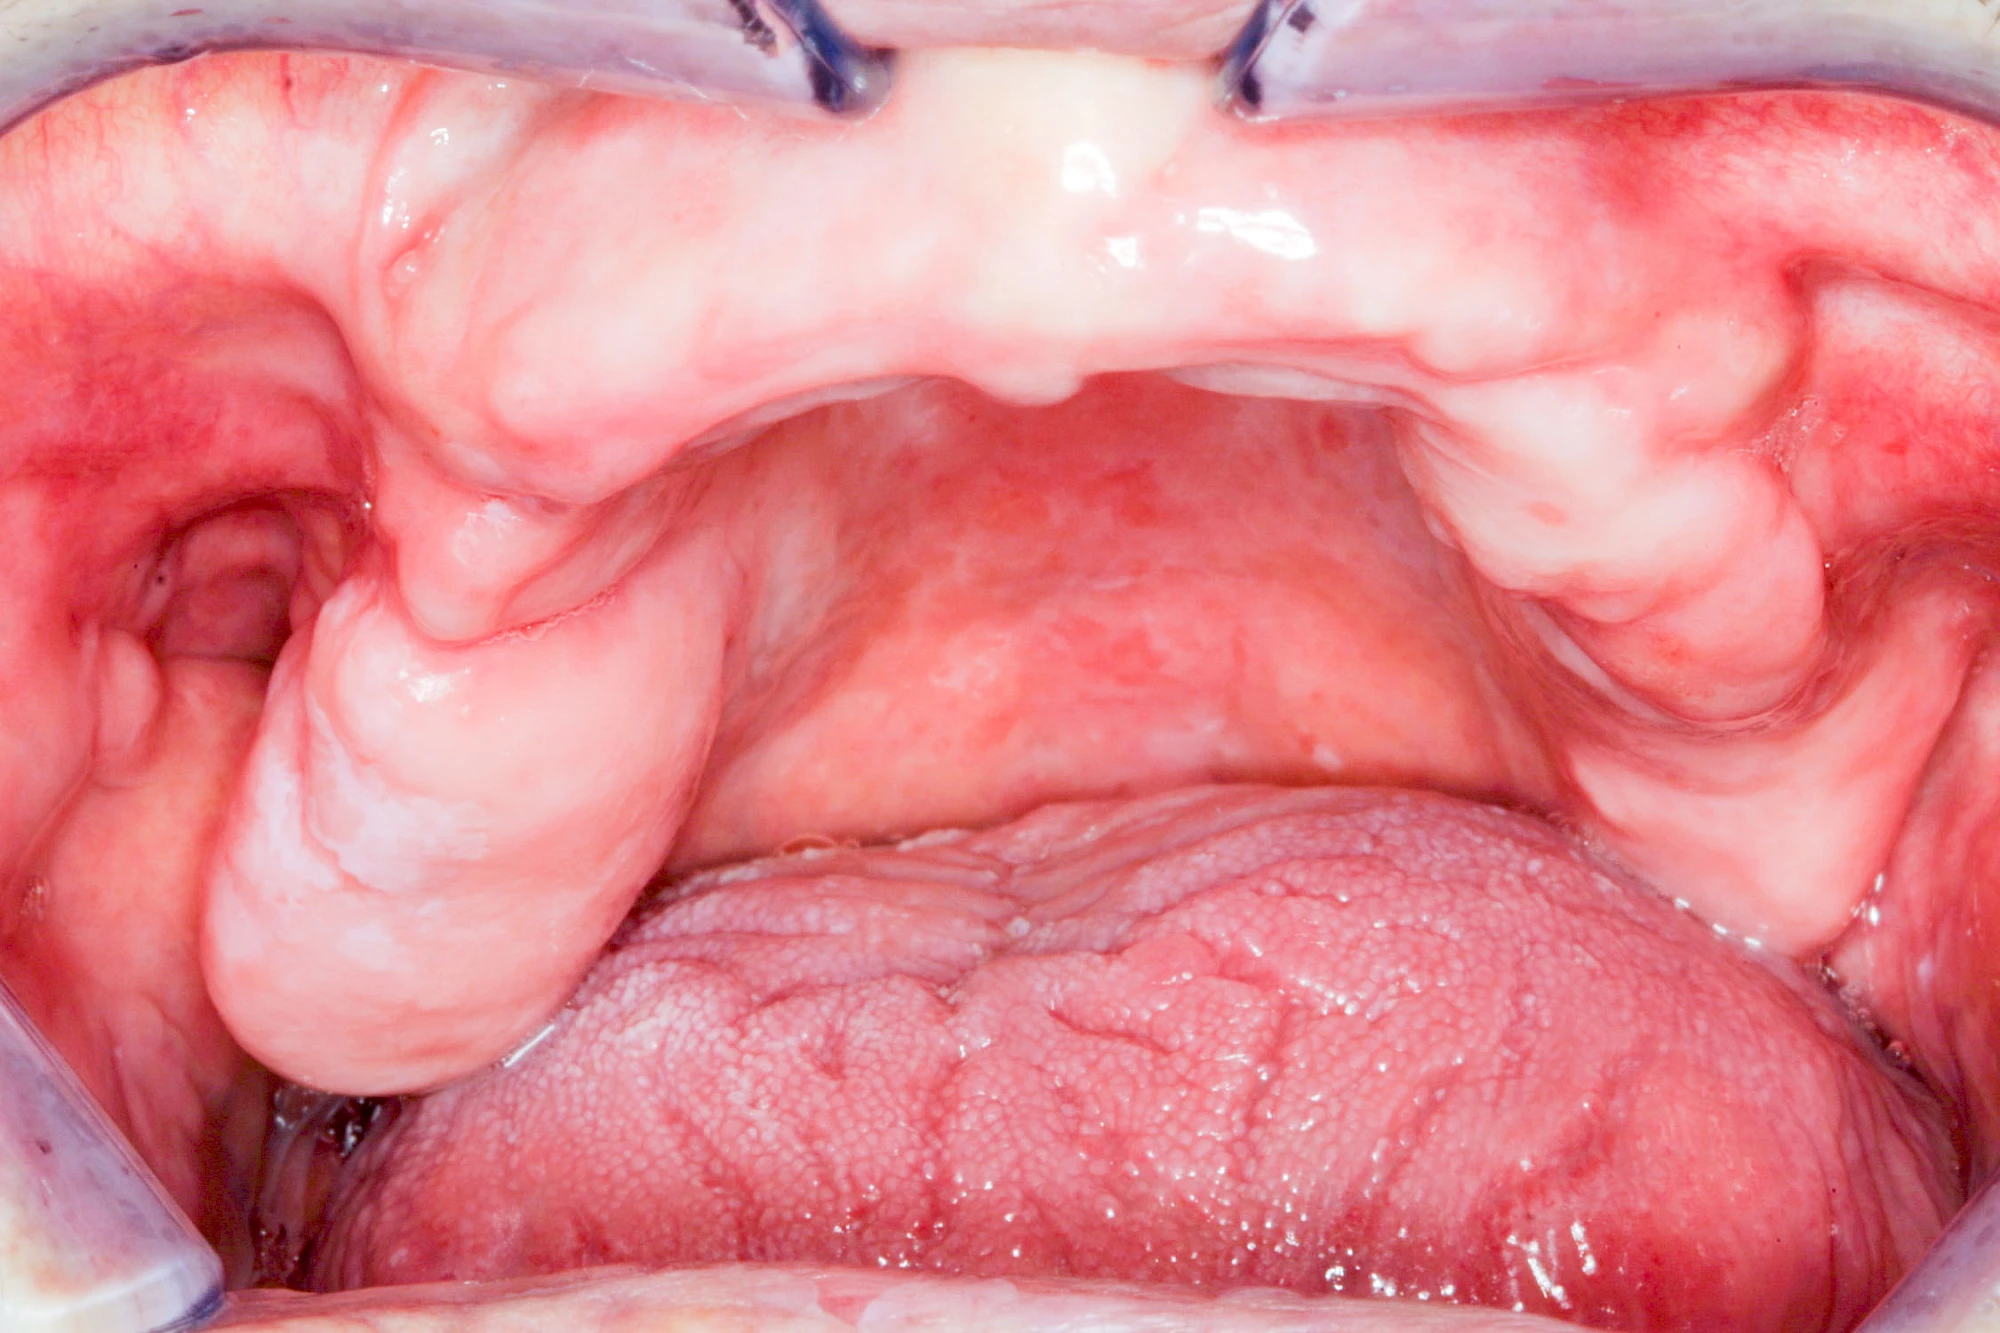

Überbein (Exostose)

Überbeine im Bereich der Kiefer sind gar nicht so selten. Häufiger im Bereich der Seitenzähne unterhalb des Zahnfleisches, aber auch in der Mitte vom Gaumen. Überbeine haben in dem Sinne keinen Krankheitswert, müssen also nicht operativ entfernt werden, wenn diese nicht stören. Überbeine können ein Anzeichen für Knirschen und Pressen sein.